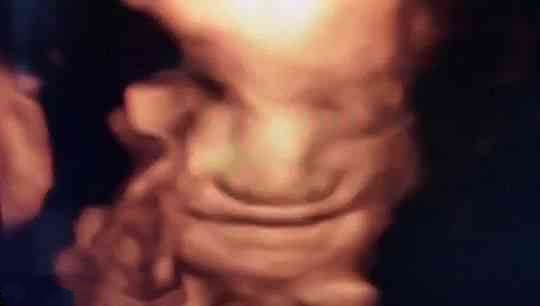

其实,关于胎宝宝在肚子里微笑,类似的报道并不少见,很多妈妈反馈过做四维时看到宝宝笑的样子,国外媒体也经常报道类似的新闻。

2003年,英国《卫报》报道,科学家用4D超声波成像系统拍到了26周宝宝微笑的图片。

2018年,英国《每日邮报》报道,一对夫妇在做四维彩超时发现宝宝咧嘴微笑,让父母感到喜出望外。

见诸各大网站的3D胎儿图像,也展示了胎儿在19周时微笑的模样,栩栩如生,惹人喜爱。

从这里看出,在做四维彩超的时候很容易捕捉到胎儿的微笑,这时不要觉得奇怪,这是胎儿正常的生理反应。